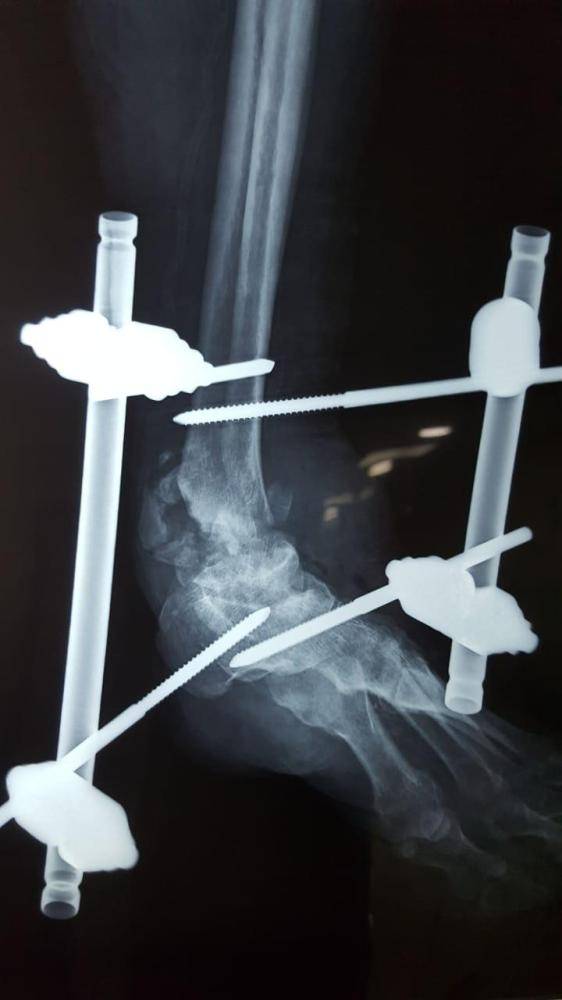

وبعد مراجعتها مستشفى دومة الجندل العام تم إجراء الفحوصات اللازمة والأشعة في عيادة العظام، وبعد عرضها على فريق من أطباء الباطنية والكلى والصدر والتخدير للإستشارة تم إجراء العملية الجراحية بعمل سمكرة لمفصل الكاحل وتثبيته بجهاز مثبت خارجي، ولله الحمد نجحت العملية والمريضة تمشي الآن وبصحة جيدة.